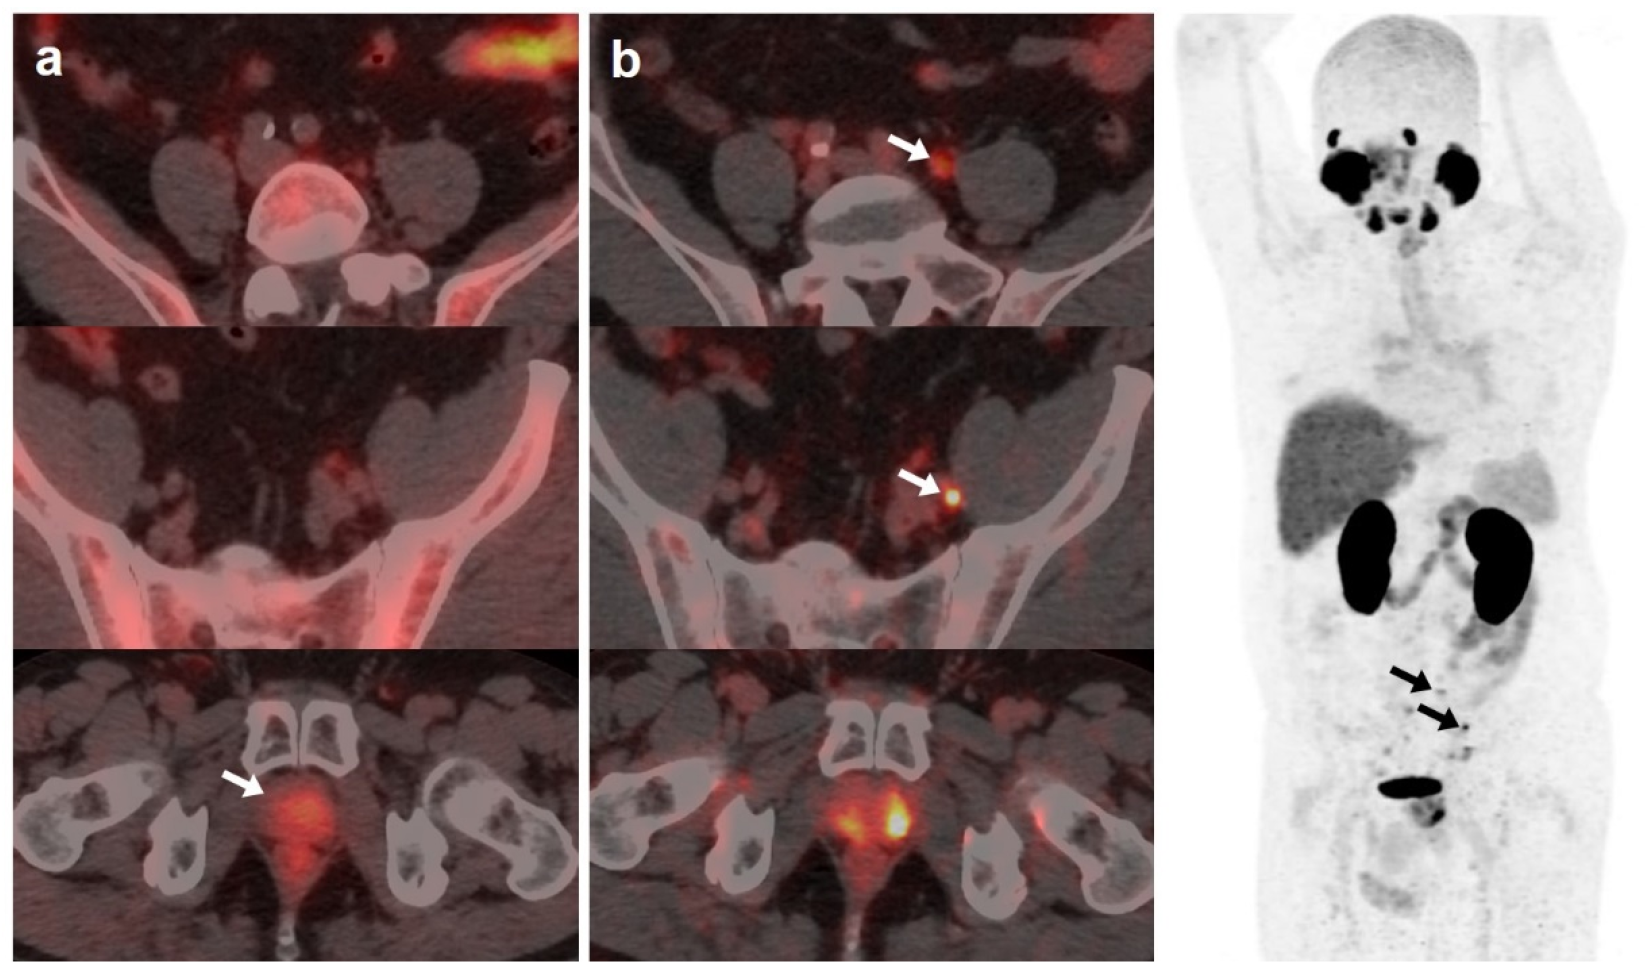

Derived from positive [18F]DCFPyL-PET/CT, 19 patients underwent additional diagnostic procedures to confirm the results: 8 by imaging (3/8 was confirmed) and 11 by histological analysis (8/11 was confirmed) (Figure 3 and Figure 4).

Figure 4.

70-year-old patient. Gleason 9 PCa, treated initially with RP and radiotherapy after his first BCR. Second BCR (PSA 0.7 ng/mL, PSAdt 5.6 months, PSAvel 0.05 ng/mL/month) with [18F]F-choline (a) and [18F]DCFPyL scans showing mediastinal lymph node tracer uptake (b) reported as inflammatory process. Follow-up was decided and PSA level continued increasing. A new [18F]DCFPyL scan (c) was performed 3 months later, showing an increase in size and metabolism of mediastinal lymph node with additional microfoci of radiotracer uptake in lung and bone, suspicious of metastases. An endobronchial ultrasound-guided lymph node biopsy confirmed prostatic origin of metastasis. ADT + Apalutamide was initiated (escalation).